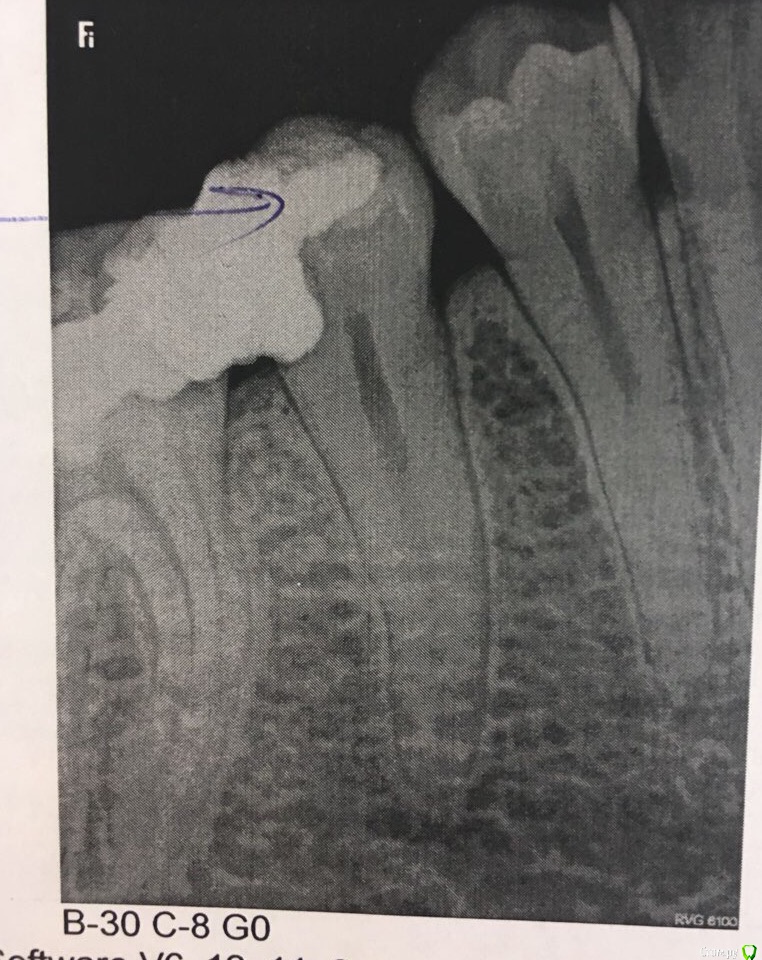

Laska86 Опубликовано 5 апреля, 2018 Автор Поделиться Опубликовано 5 апреля, 2018 Снимок Ссылка на комментарий

Laska86 Опубликовано 5 апреля, 2018 Автор Поделиться Опубликовано 5 апреля, 2018 Была еще у 2 врачей.Один говорит, можно пломбу, цемент и тп, но не кнрамич вкладку на мертвый зуб.Другой говорит, кариес почти до костной ткани глубиной, однозначно ничего уже не сделать. Все меры временные, все приведет к загноению. Предложили 1 вариант. Брекетами вытянуть этот зуб вверх, удалив нерв и пролечить как обычный кариес, спилить и поставить коронку.Ваше мнение?(((( морально не готова удалять ((( Ссылка на комментарий

AndyAndy Опубликовано 5 апреля, 2018 Поделиться Опубликовано 5 апреля, 2018 Смысл восстановления разрушенных тканей зуба (пломба, керамич вкладка, коронка) состоит в том, чтобы обеспечить максимальный герметизм и не допустить подтекания жидкости. Иначе возникает вторичный кариес между реставрацией и тканями зуба, который приводит к выпадению пломб и вкладок, расцементировке коронок и в конечном счете к удалению зуба. В вашем случае зуб действительно разрушен значительно ниже уровня десны, что приведёт к сложностям изоляции зуба при постановке пломбы или керамич вкладки, а также сложно качественно снять оттиск под коронку.Есть 2 варианта решения таких проблем, сохраняя при этом зуб: 1) хирургическое удлинение коронковой части зуба(в вашем случае не показано)2) ортодонтическая экструзия зуба(то, что вам предложили) - ваш вариант. Зуб действительно придётся спилить по высоте. Поэтому +1 за коронку Ссылка на комментарий

AndyAndy Опубликовано 5 апреля, 2018 Поделиться Опубликовано 5 апреля, 2018 Поднимать необходимо до того состояния, которое позволит установить коронку (по снимку 1.5-2мм). Высота коронки в итоге не изменяется - корень становится короче. В вашем случае переживать особо не стоит - зуб не имеет видимых пародонтальных проблем и думать о его "выпадении" не нужно. По поводу остальных вопросов - на них вам ответит лечащий врач, имея дополнительные объективные данные. Вообще меньше читайте страшилки из интернета, доверяйте вашему доктору. Он дело говорит. Ссылка на комментарий